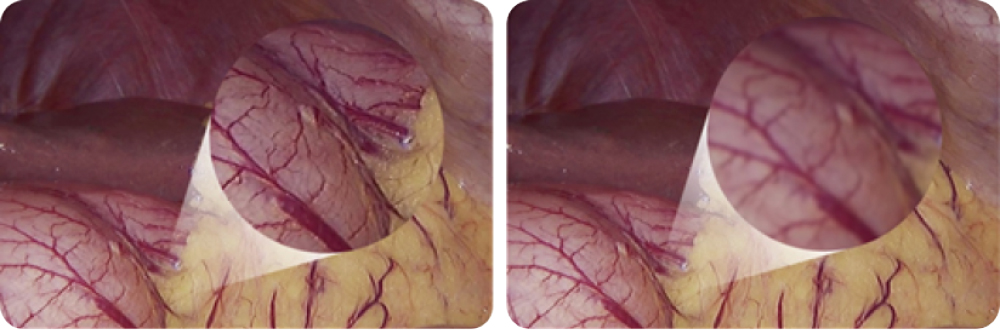

市面上感光元件主要分为CMOS或者CCD两种。而CMOS具有较好的分辨率,呈现更真实色彩与更清晰组织细节,同时提供更快的聚焦时间与更实时的成像。

CMOS 图像表现

CCD 图像表现